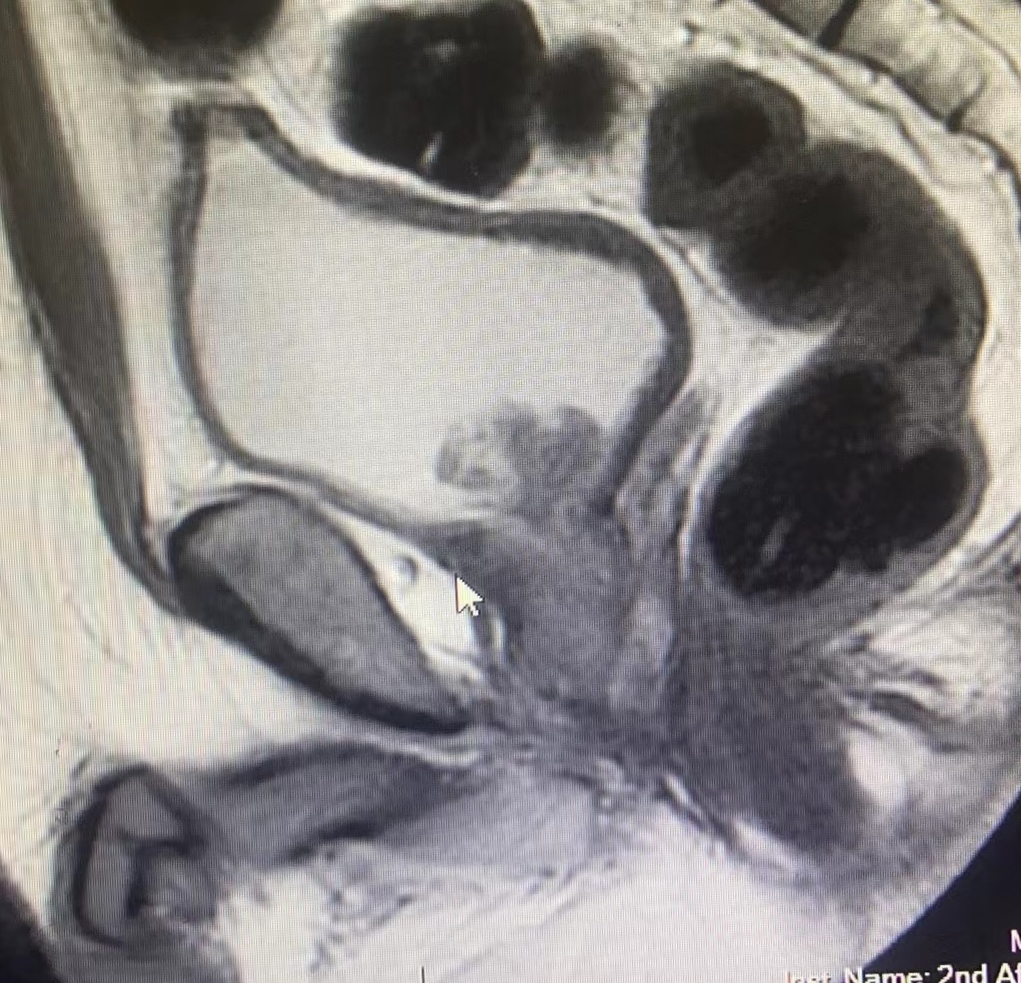

入院后,詹辉教授团队对李先生进行了详细的病史询问和术前评估检查。盆腔磁共振检查发现,膀胱呈现多发肿瘤,最大瘤体4.0x2.7x2.2cm,肿瘤组织向下侵犯前列腺部。取活检后病理结果提示:膀胱高级别尿路上皮癌,术前诊断为:膀胱高级别尿路上皮癌(T3NxMx)。同时入院检查发现患者心脏功能极差,超声心动图提示:左心室壁弥漫性运动减弱,心脏射血分数27%,不到正常人心脏射血功能的一半;动态心电图提示:频发室性过早搏动,心脏自主神经功能调节失调;冠脉CT提示:左前降支中重度狭窄,N端脑钠肽前体:1990pg/ml。此外由于肿瘤侵犯前列腺,长期梗阻导致患者肾功能不全、尿路耐药摩根氏菌感染,同时还合并有高血压2级、2型糖尿病、中度肺通气功能障碍、支气管扩张症等疾病。